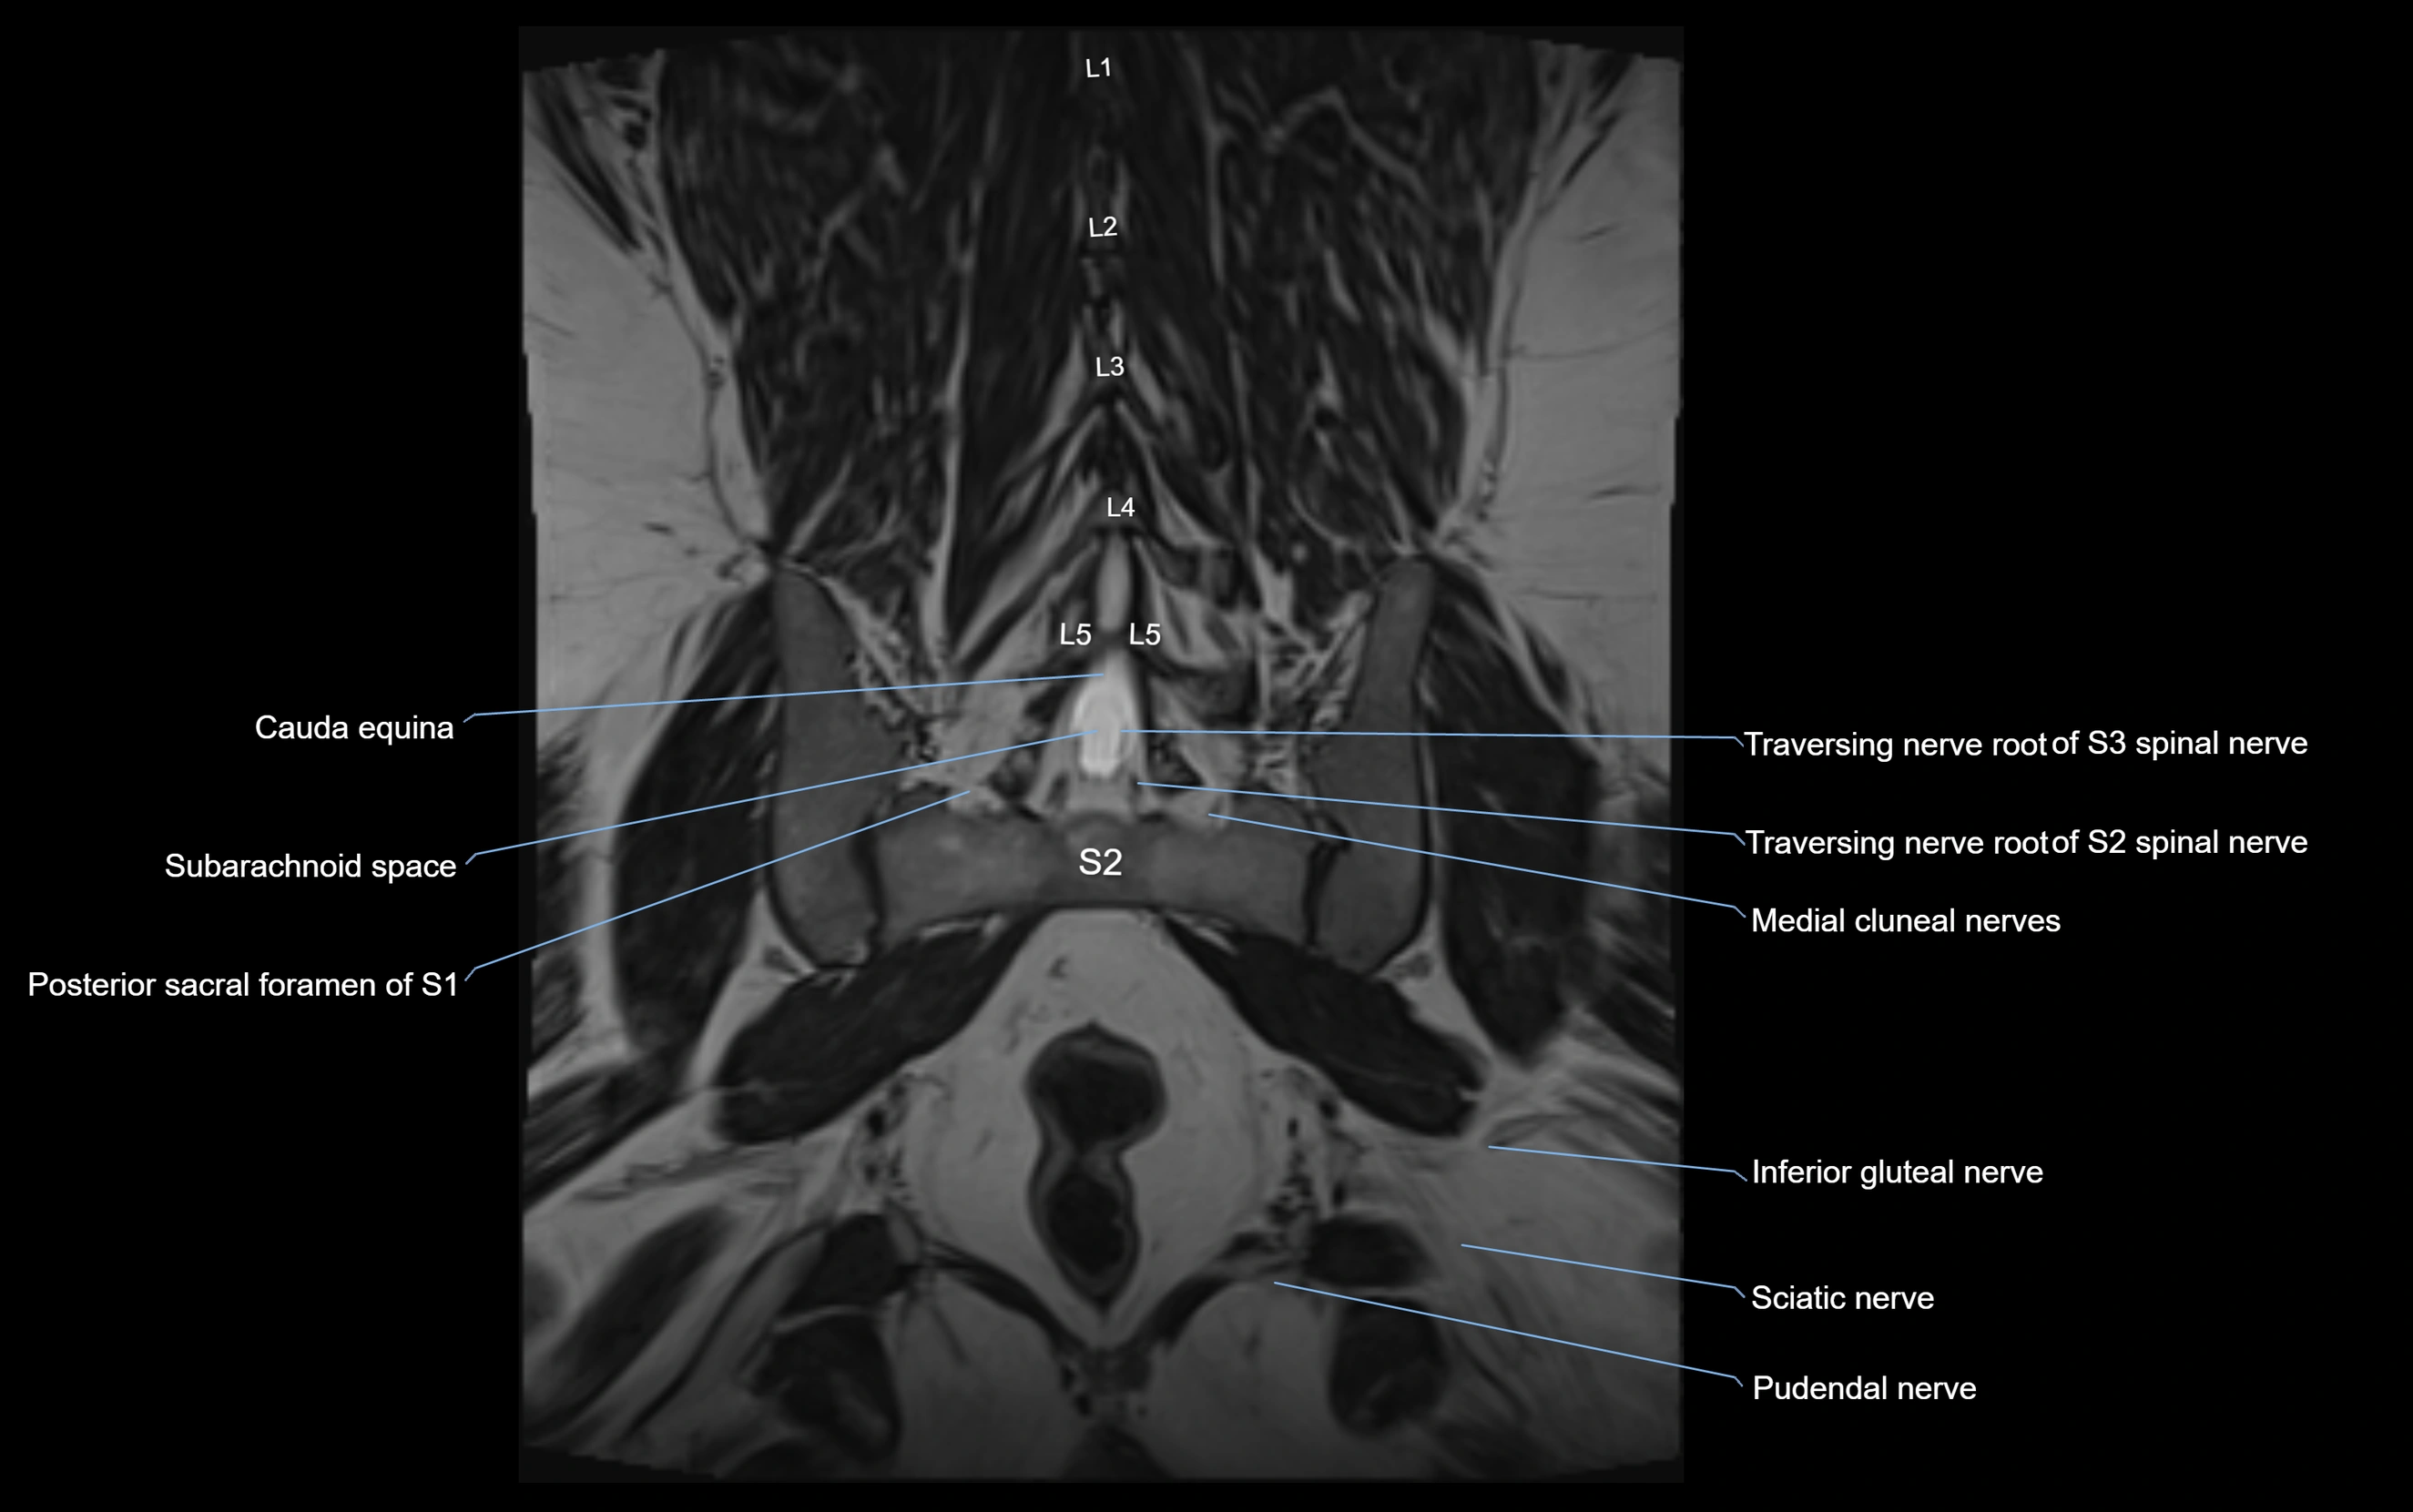

MRI image

image